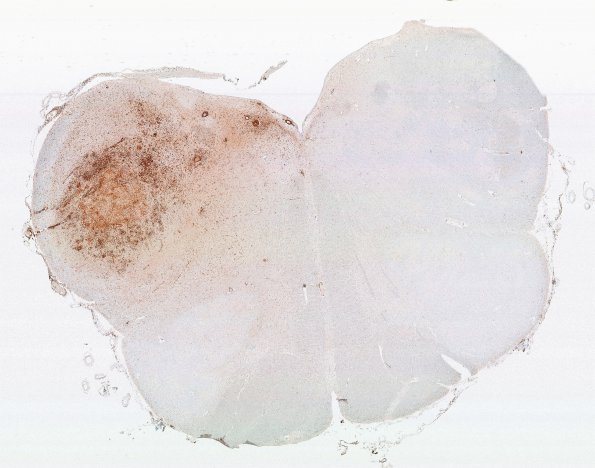

Washington University Experience | NEOPLASMS (HEMATOLYMPHOID) | Lymphomatoid Granulomatosis | 1K8 LYG (Case 1) Medulla N8 H&E WM

1K8-10 Whole mount, low and high magnification images are shown stained for CD68 which labels microglia and macrophages, not typically the neoplastic B cells. (CD68 IHC)